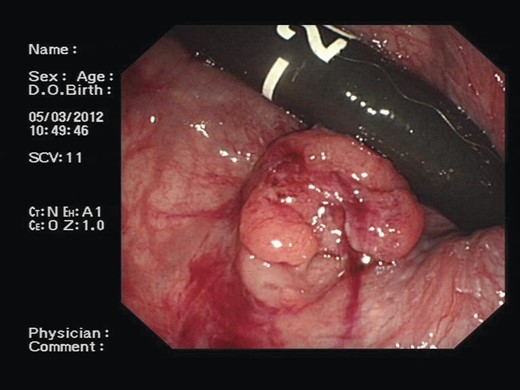

A 71-year-old asymptomatic gentleman with known history of colonic polyps underwent a follow-up surveillance colonoscopy through the BCSP. He had a background of type 2 diabetes mellitus, ischaemic heart disease and diverticular disease. Colonoscopy revealed a 1-cm firm polypoid mass at the ano-rectal junction (Fig. 1). Subsequent endoscopic mucosal resection was performed and the tissue was sent for histological analysis. This confirmed a tubulo-villous adenocarcinoma. As per national guidelines the patient underwent a staging computed tomography (CT) scan. This revealed a 10 × 15 cm homogenous mass arising from within the pelvis (Fig. 2). The mass appeared to be continuous with a neural foramen arising from the sacrum. Further imaging confirmed the mass extending into sacral segment S1 inferiorly, lumbar segments L4 superiorly and the bladder anteriorly. A regional multidisciplinary team discussion concluded that abdominoperineal resection (APR) was the most appropriate surgical approach for removal of both pathologies in their entirety.

A colonoscopic image demonstrating ∼1-cm polypoid mass at the ano-rectal junction.